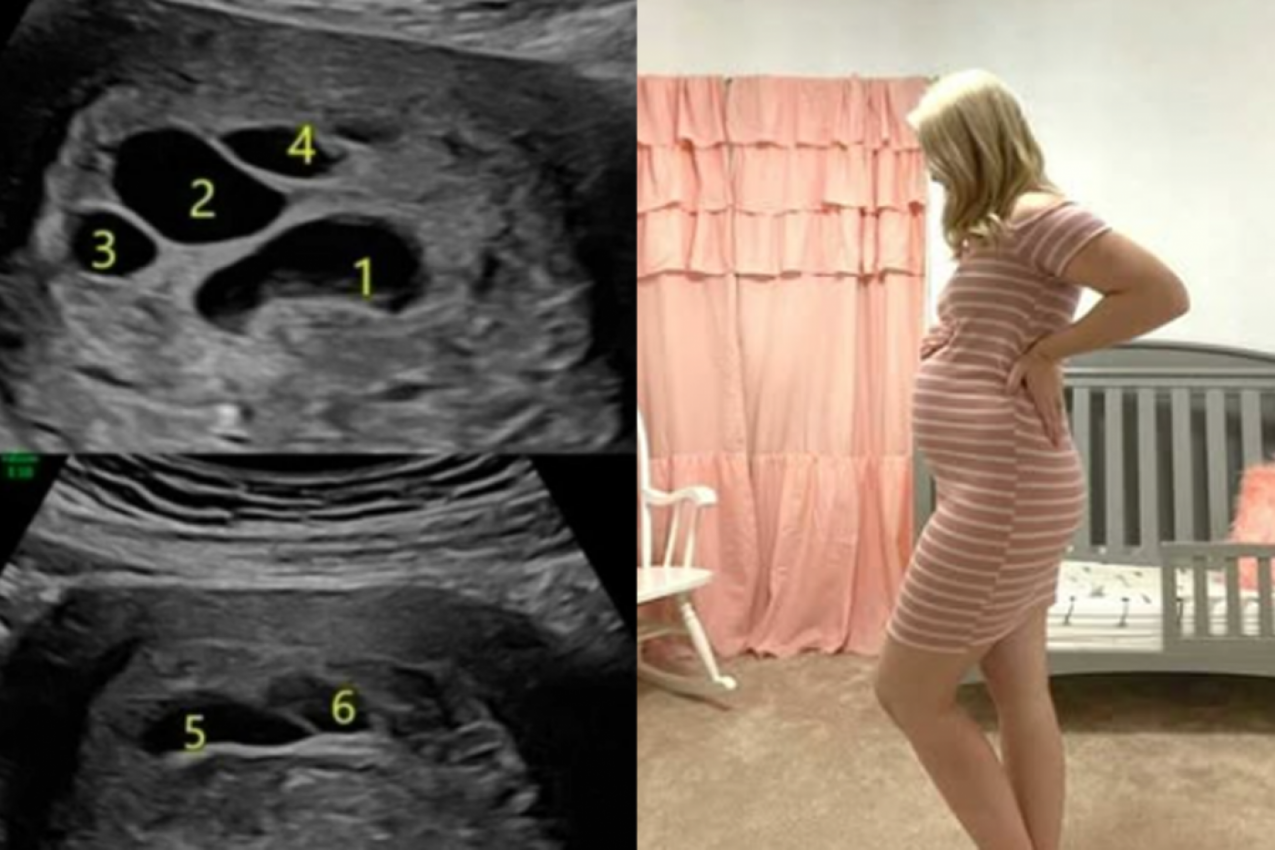

- Kad sam ih upitala o čemu se radi, samo su mi okrenuli ekran. Na ultrazvuku se videla moja beba, ali i šest misterioznih crnih "rupa"! Bila sam šokirana, a ginekolog nije mogao da mi objasni o čemu se radi. Kako je rekao, nikad tako nešto nije video. Te rupe su trebale da budu mesto za nove, druge bebe, samo što njih nije bilo - kazala je Bri.

Ona ne krije da je bila zgranuta slikom koju gleda. Bila je uplašena za svoju bebu, posebno što niko od lekara nije mogao da joj objasni o čemu se radi. Mnogi iskusni ginekolozi koje je kontaktirala su joj kazali da tokom svoje karijere nisu videli ništa slično.

- Beba je rasla kako je trudnoća napredovala i kako se činilo čudne rupe joj ni najmanje nisu smetale. Svi parametri trudnoće bili su odlični, osim tih rupa. A, onda sam u osmom mesecu trudnoće otišla na još jedan, ko zna koji po redu ultrazvuk, i rupe su jednostavno nestale! Tek to niko nije mogao da objasni, kao da se desilo neko čudo - dodala je ona.